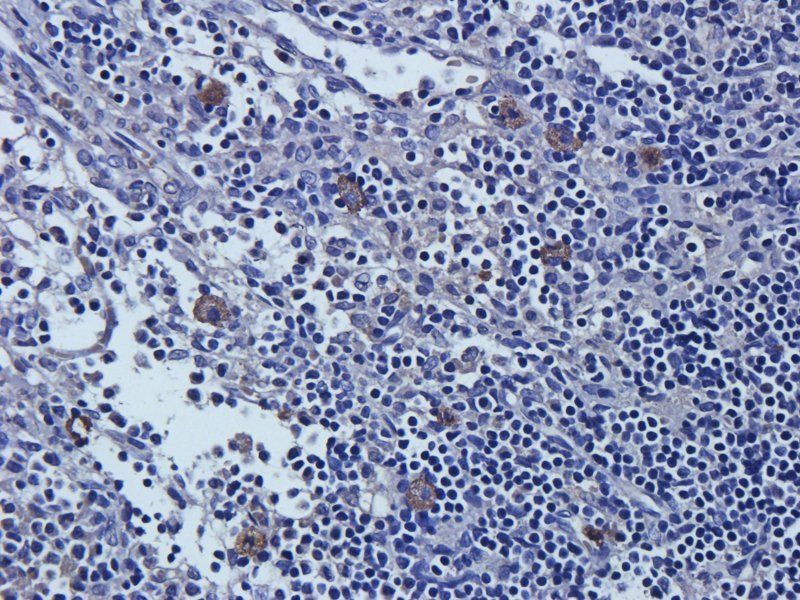

应用稀释比例:WB: 1:200-2000, IHC-P: 1:100-500, IF/ICC: 1:100-500

文献和实验3) 依赖性细胞死亡来介导中暑。 热应激通过热休克转录因子 1 (HSF1) 增加 ZBP1 的表达,并通过独立于核酸感应作用的机制激活 ZBP1。ZBP1、RIPK3 或混合谱系激酶域样 (MLKL) 和 caspase-8 的缺失降低了热应激诱导的循环衰竭、器官损伤和致死率。因此,ZBP1 似乎具有协调宿主对热应激反应的第二个功能。 临床上,中暑的特征是极度高热、全身炎症反应、循环衰竭、出血和凝血障碍,以及热相关细胞毒性、炎症和弥散性血管内凝血 (DIC) 之间复杂相互作用导致的多器官

,4046 个蛋白质被定量。与对照组相比,CUMS 组在 1.5 倍变化 (> 1.50 或 差异蛋白验证:免疫荧光证实,与对照组相比,海马 CA1 和 DG 亚区的神经元损失显著。对 RIP3、MLKL 和 p-MLKL 及与铁稳态失调和脂质过氧化相关指标,包括 Ftl1、MDA、GSH 和 GPX4 等进行 WB 验证,结果表明铁死亡和坏死与慢性应激诱导的抑郁有关。 6.2、IF 3-5 分文章:蛋白质组学+代谢组学 蛋白质组学和代谢组学检测 分析差异蛋白,对差异蛋白进行